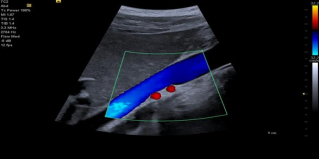

*在成像功能上,除高级空间符合成像 AdvSieclear、动态组织对比增强 DTCE 等西门子的特色成像功能外,在 Juniper 上我们新增了 DynamicPersistence 动态余辉和 Auto Flash Color Artifact Suppression 自动闪烁伪像抑制技术,来调节和优化图像的信噪比和彩色的敏感性。

• Dynamic Persistence 动态余辉技术可抑制探头或病人移动造成的拖帧,并在无明显运动时降低 2D的噪声,提升彩色的敏感性

• Auto Flash Color Artifact Suppression 自动闪烁伪像抑制检测和防止与探头和病人运动相关的运动伪影,并在没有检测到运动时提高颜色成像灵敏度检测和防止与探头和病人运动相关的运动伪影,并在没有检测到运动时提高颜色成像灵敏度